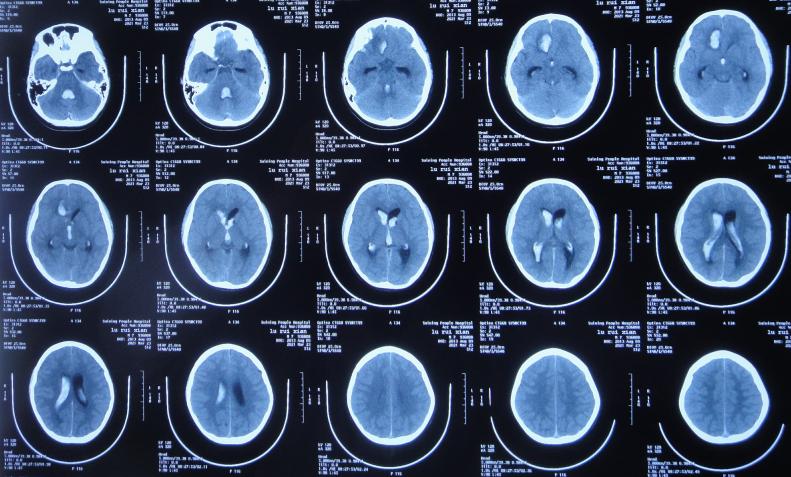

患者2021年3月23日早起突发头痛,意识不清,急送至江苏省徐州市睢宁县某医院,查脑CT示脑出血( 图-1 );既往史有癫痫病史。

图-1: 2021年3月23日脑CT